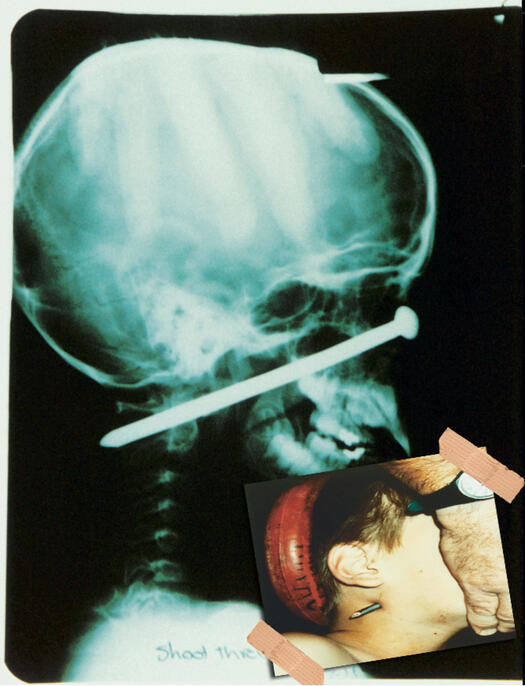

ЕКСПОНАТ 2

Безопасна игла в гърлото

Великобритания. Историята мълчи как се е случило. Докторите отново правят чудо и жената си тръгва жива, здрава и унизена от болницата.